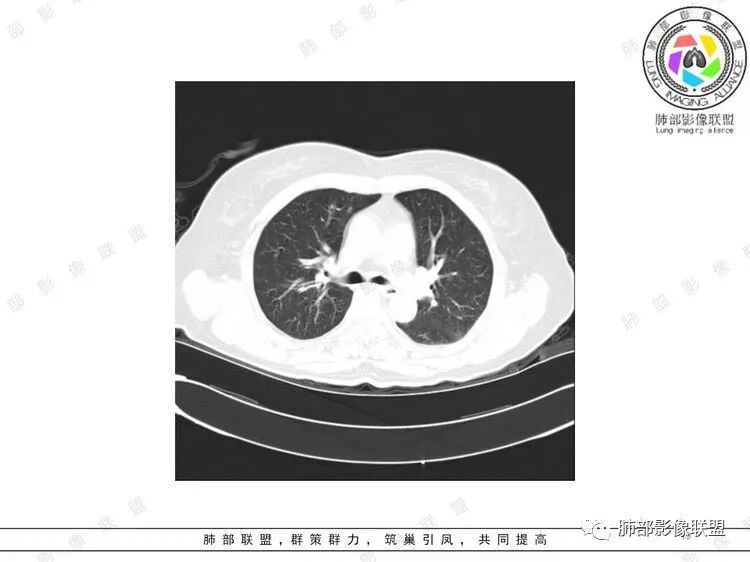

胸CT:双中下肺支气管壁明显增厚,双下肺胸膜下可见实变区。部分病变呈楔形影。

双肺支气管管壁弥漫性增厚,管腔狭窄,下叶为主,伴多发高密度结节影,边缘模糊,双肺支气管血管束明显增粗,临床症状咳嗽低热,有血尿,首先考虑血管炎

支气管壁增厚,两下肺为主,沿支气管血管束分布斑片状、结节状病变,中轴间质增厚。疾病谱可能有:1.气道来源疾病:结核、曲霉、支原体等;2.间质来源疾病:血管、淋巴系统。结合有血尿,使用激素后尿色变淡、抗生素治疗效果差等病史,考虑血管炎可能性大。

影像上:多发结节沿血管分布;双下叶支气管血管束简直增厚,偏血管,支气管通畅

首先肺部气道来源的病变不符合

因为支气管壁增厚,远端应该小气道病变,这个不是,反而是血管增粗明显

加上结节的分布,支持血管相关病变